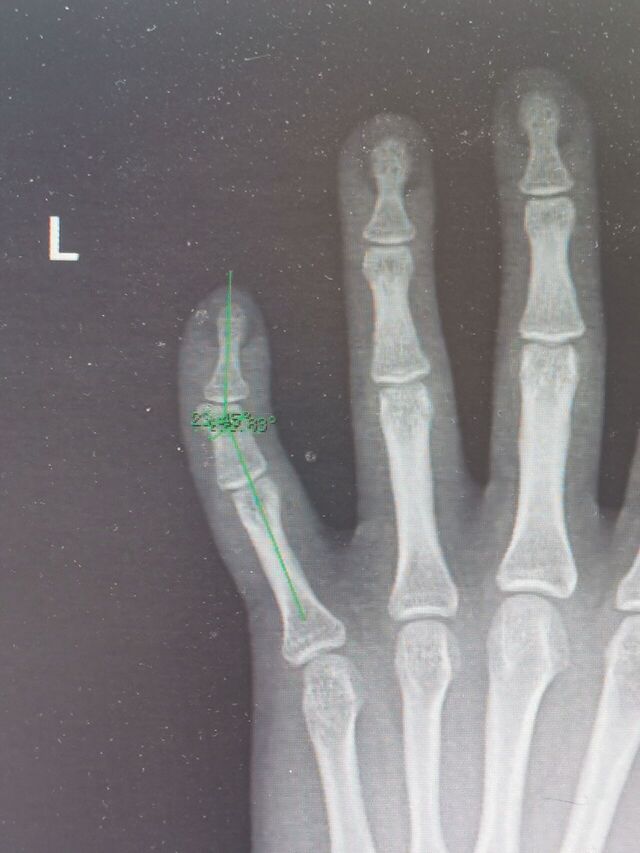

另一例足拇趾多趾畸形术后

微信图片_20240330000150.jpg